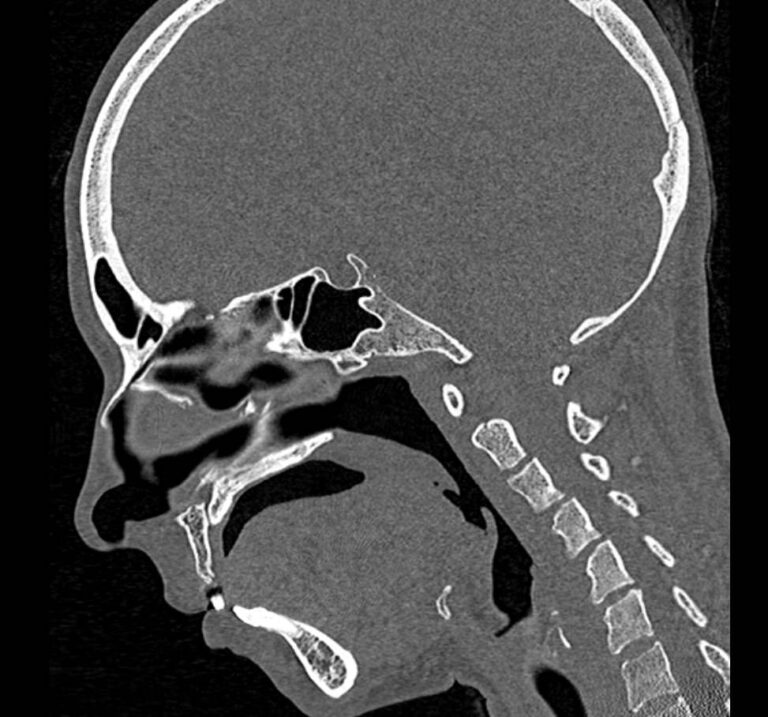

Мультиспиральная компьютерная томография относится к высокоинформативным лучевым методам исследования, то есть основана на применении рентгеновского излучения и различной способности тканей поглощать рентгеновские лучи. Костные структуры обладают наибольшей плотностью по сравнению с другими тканями, поэтому в большей степени поглощают рентгеновские лучи и лучше всего визуализируются при данном исследовании. Благодаря этому КТ позволяет детально изучить кости лицевого черепа, а также углубления, которые являются вместилищем для важных органов (глазницы, полость носа, ротовая полость).

КТ мягких тканей лица является наиболее информативным методом диагностики травматических повреждений лица, посттравматических деформаций, аномалий развития, инородных предметов в носовой полости и околоносовых пазухах. Кроме того, мультиспиральная КТ применяется для выявления скрытых воспалительных процессов, нарушений кровообращения в области лица, а также используется при планировании оперативного вмешательства (в том числе, пластических операций) и в дальнейшем применяется в послеоперационном периоде для оценки успешности проведенной операции.

Детальные изображения костей лицевого черепа и мягких тканей лица получаются за счет вращения трубки томографа с излучателями рентгеновских лучей вокруг объекта исследования. В аппаратах увеличено количество сверхчувствительных детекторов, позволяющих производить множество послойных снимков с толщиной среза от 0,5 мм, которые затем преобразуются в трехмерные пространственные модели лицевого черепа с окружающими тканями. Такие инновационные возможности аппаратов обеспечивают проведение точной и достоверной диагностики.